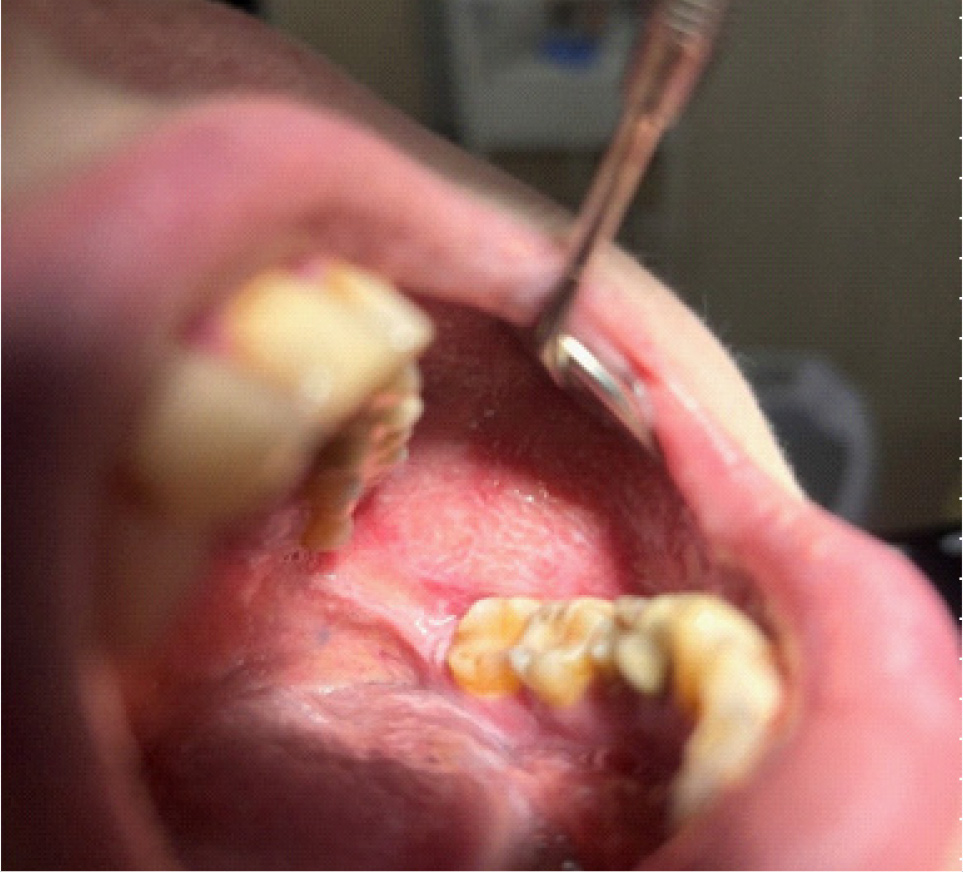

В полости рта: лунки 3.2, 3.3 зубов в субтотальном остеонекрозе альвеолярной части нижней челюсти слева. На слизистой оболочке альвеолярной части нижней челюсти справа определяется язва размером до 1,0 см с инфильтрированными краями, дно язвы выполнено некротическими массами (рис. 7).

Рис. 7. Клинические проявление бисфосфонатного остеонекроза нижней челюсти слева

Пальпация безболезненная. В связи с отказом от проведения рентгенологического исследования нижней челюсти предоставить данные не представляется возможным.